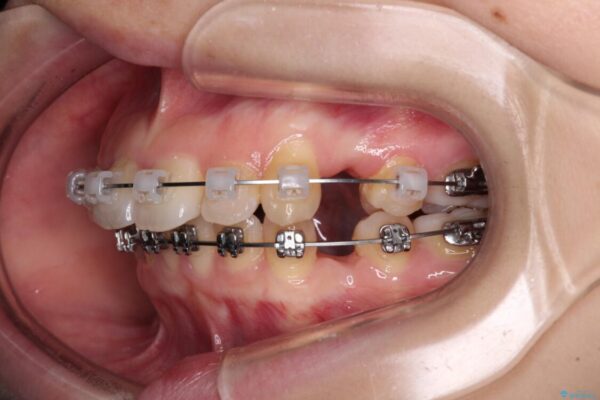

治療途中

• 【モニター】口が閉じられない ワイヤー装置での抜歯矯正 治療途中画像

上下前歯が著しく前突している状態であったので、上下左右の第1小臼歯4本を抜歯し、ワイヤー装置にて矯正治療を行うこととしました。

舌の突出癖により、前突になったと考えられたため、舌のトレーニングをしっかりと行うよう指導しました。

※写真にある上顎装置はメタルブラケットではありません。メーカー在庫都合などにより別の装置を使用しております。